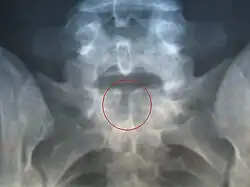

Röntgenfoto van een persoon met spina bifida occulta ter hoogte van S1